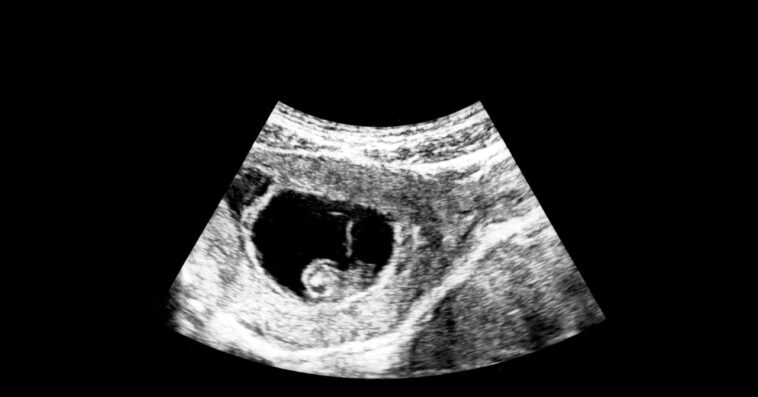

Those using IVF can see which embryo is least likely to develop cancer and other diseases. But can protecting your child slip into playing God?

Genetic Screening Now Lets Parents Pick the Healthiest Embryos